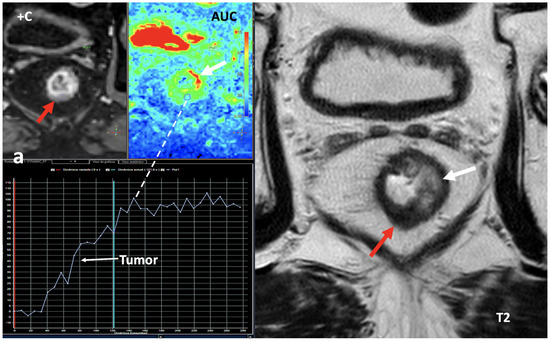

Figure 12. Breast 120 kVp-like (a) and color-coded iodine map (b) images. Breast lesion detection. Multicentric left breast invasive ductal carcinoma can easily be detected based on iodine uptake (dotted circle) compared to the 120 kVp-like image, where the diagnosis is challenging. - Currently, there is not a widely reported use of DECT in clinical management of prostate cancer. However, DECT imaging may facilitate the depiction of focal areas of increased enhancement in the periphery of the prostate in contrast-enhanced CT that may represent a clinically significant cancer and deserve further workup [42] (Figure 13).

Figure 13. Prostate cancer (PCa) diagnosis. Incidental detection of a focal area of increased enhancement in the periphery of the prostate in contrast-enhanced CT may represent a clinically significant cancer (arrows) deserving of further workup. DECT imaging-based data such as a monoenergetic image at low energy values (e.g., 45 keV) and color-coded iodine map facilitate its detection. Note the difference between the spectral curve of the tumor (yellow curve, 1) and the normal parenchyma (blue curve, 2). Biopsy evidenced a prostate cancer having a Gleason score of 3 + 4. - LN characterization is challenging in oncologic imaging. Apart from morphologic criteria, different DECT parameters have been used, including iodine concentration, fat fraction, and similarity to the primary tumor [41,43]. Sauter et al. [44] evaluated standard values for of iodine concentration for healthy LNs in different anatomic areas that could be used to differentiate between healthy and pathological LNs. Recent studies have suggested lower iodine concentration in metastatic LNs compared to benign LNs [45]. However, the value of DECT imaging in differentiating malignant from non-malignant LNs seems to be limited and depends on the tumor type and technical features such as the protocols used for acquisition and contrast injection (Figure 14).